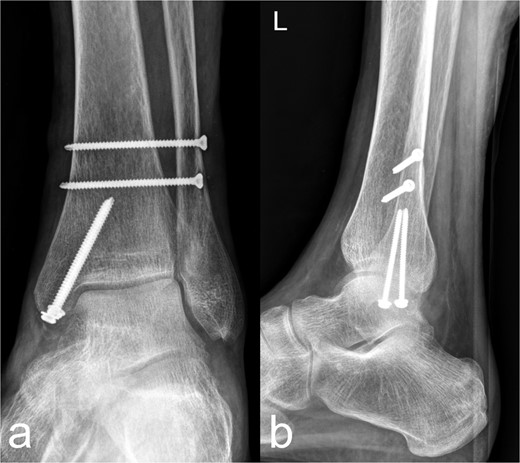

An osseous fragment of the medial malleolus with Volkmann’s triangle was continuously adapted with two lag screws. In addition, the syndesmosis tibiofibularis was stabilized with two positioning screws (Fig. 3a and b).

Treatment patterns of the distal tibia and Maisonneuve fracture (44C2.2 and Weber C). As a secondary finding, there is an osteopenic bone texture of the imaged skeletal area. (a) The anterior-posterior image shows an anatomical reposition of the medial malleolus, which was fixed with two lag screws. Two syndesmosis screws are located slightly further cranially. (b) The lateral image shows a continuous fragment adaptation of the medial malleolus/Vollkmann's triangle. The screws inserted at the level of the medial malleolus and proximal to the syndemosis tibiofibularis show a regular position.